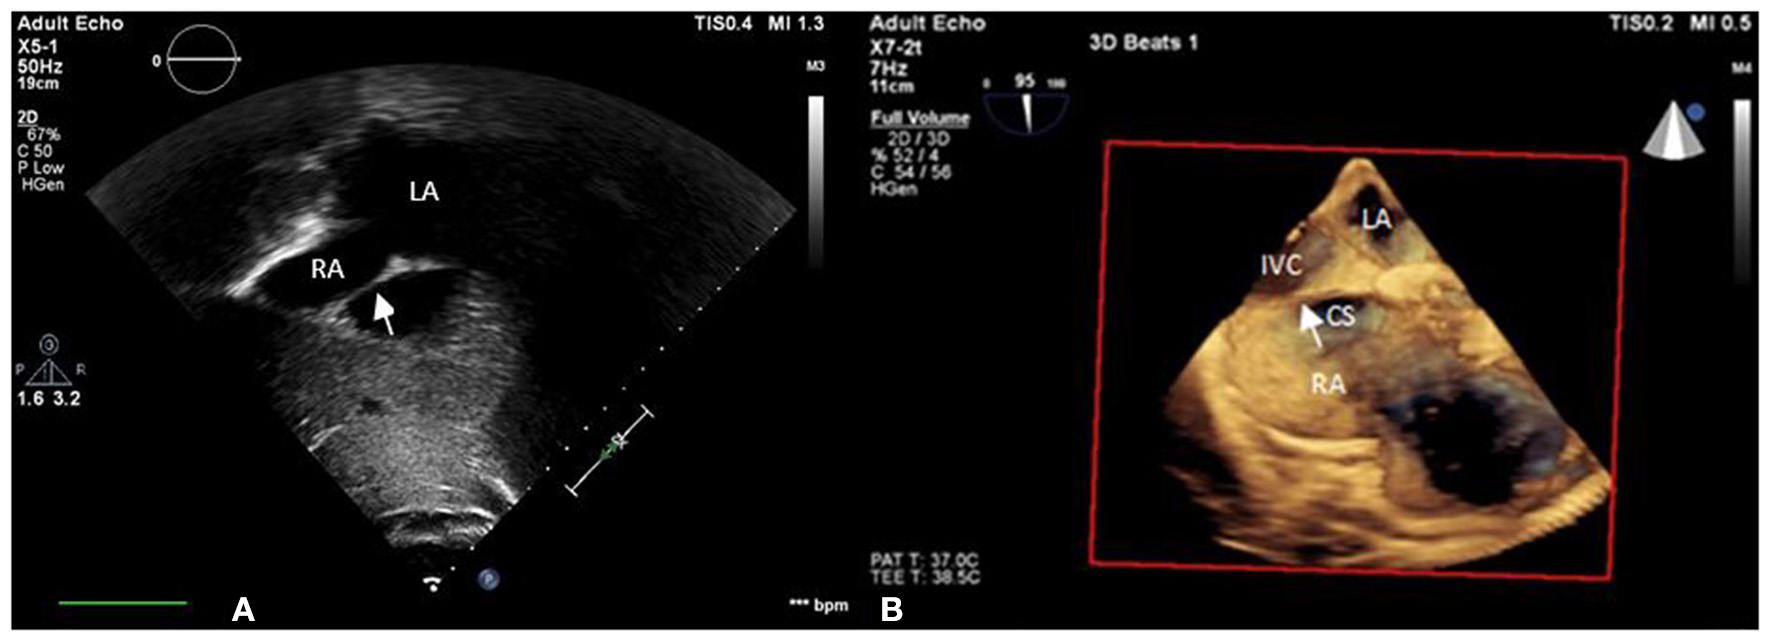

A 55-year-old female patient came to our hospital with a complaint of chest discomfort for 2 days. The electrocardiogram (ECG) revealed an incomplete right bundle branch (iRBBB) without ST segment elevation. Troponin-I, creatine kinase (CK), and creatine kinase-MB (CK-MB) levels were in the normal range. Chest X-ray revealed right ventricle hypertrophy (RVH) with prominent pulmonary congestion. Two secundum type ASDs with membranous remnants at the right atrium were noted in TTE. TEE was arranged for the membranous remnants at the right atrium and revealed double ASDs with iCTD at the connection of the right atrium and inferior vena cava (Figures 1A,B). Cardiac CT showed double ASDs, which were 21.2 and 13.6 mm in size, with iCTD (Figures 2A,B). During catheterization, no pulmonary hypertension was found, and the size of the larger ASD under balloon sizing was 29.2 mm. The ratio of pulmonary flow to systemic flow was 1.9:1. Therefore, a 30-mm Lifetech device was chosen to close these two ASDs. We chose a 7 French sheath to pass the larger ASD from the RA to LA and deploy the device to close the ASDs without detachment. However, transient heart ischemia with presence of ST segment elevation (Figure 3A) was noted and coronary sinus obstruction by the device was thought to be the cause. The shape of the device was also not feasible and many residual shunts were noted. Partial involvement of iCTD in the process of device deployment, which resulted in the obstruction of coronary sinus, was determined (Figure 4A). Hence, we withdrew the device immediately and the ST segment elevation recovered (Figure 3B).

Figure 1

iCTD (arrow) at the connection of the right atrium and inferior vena cava is shown in (A) transthoracic echocardiogram (TTE) and (B) three-dimensional TEE. LA, left atrium; RA, right atrium; CS, coronary sinus; IVC, inferior vena cava.